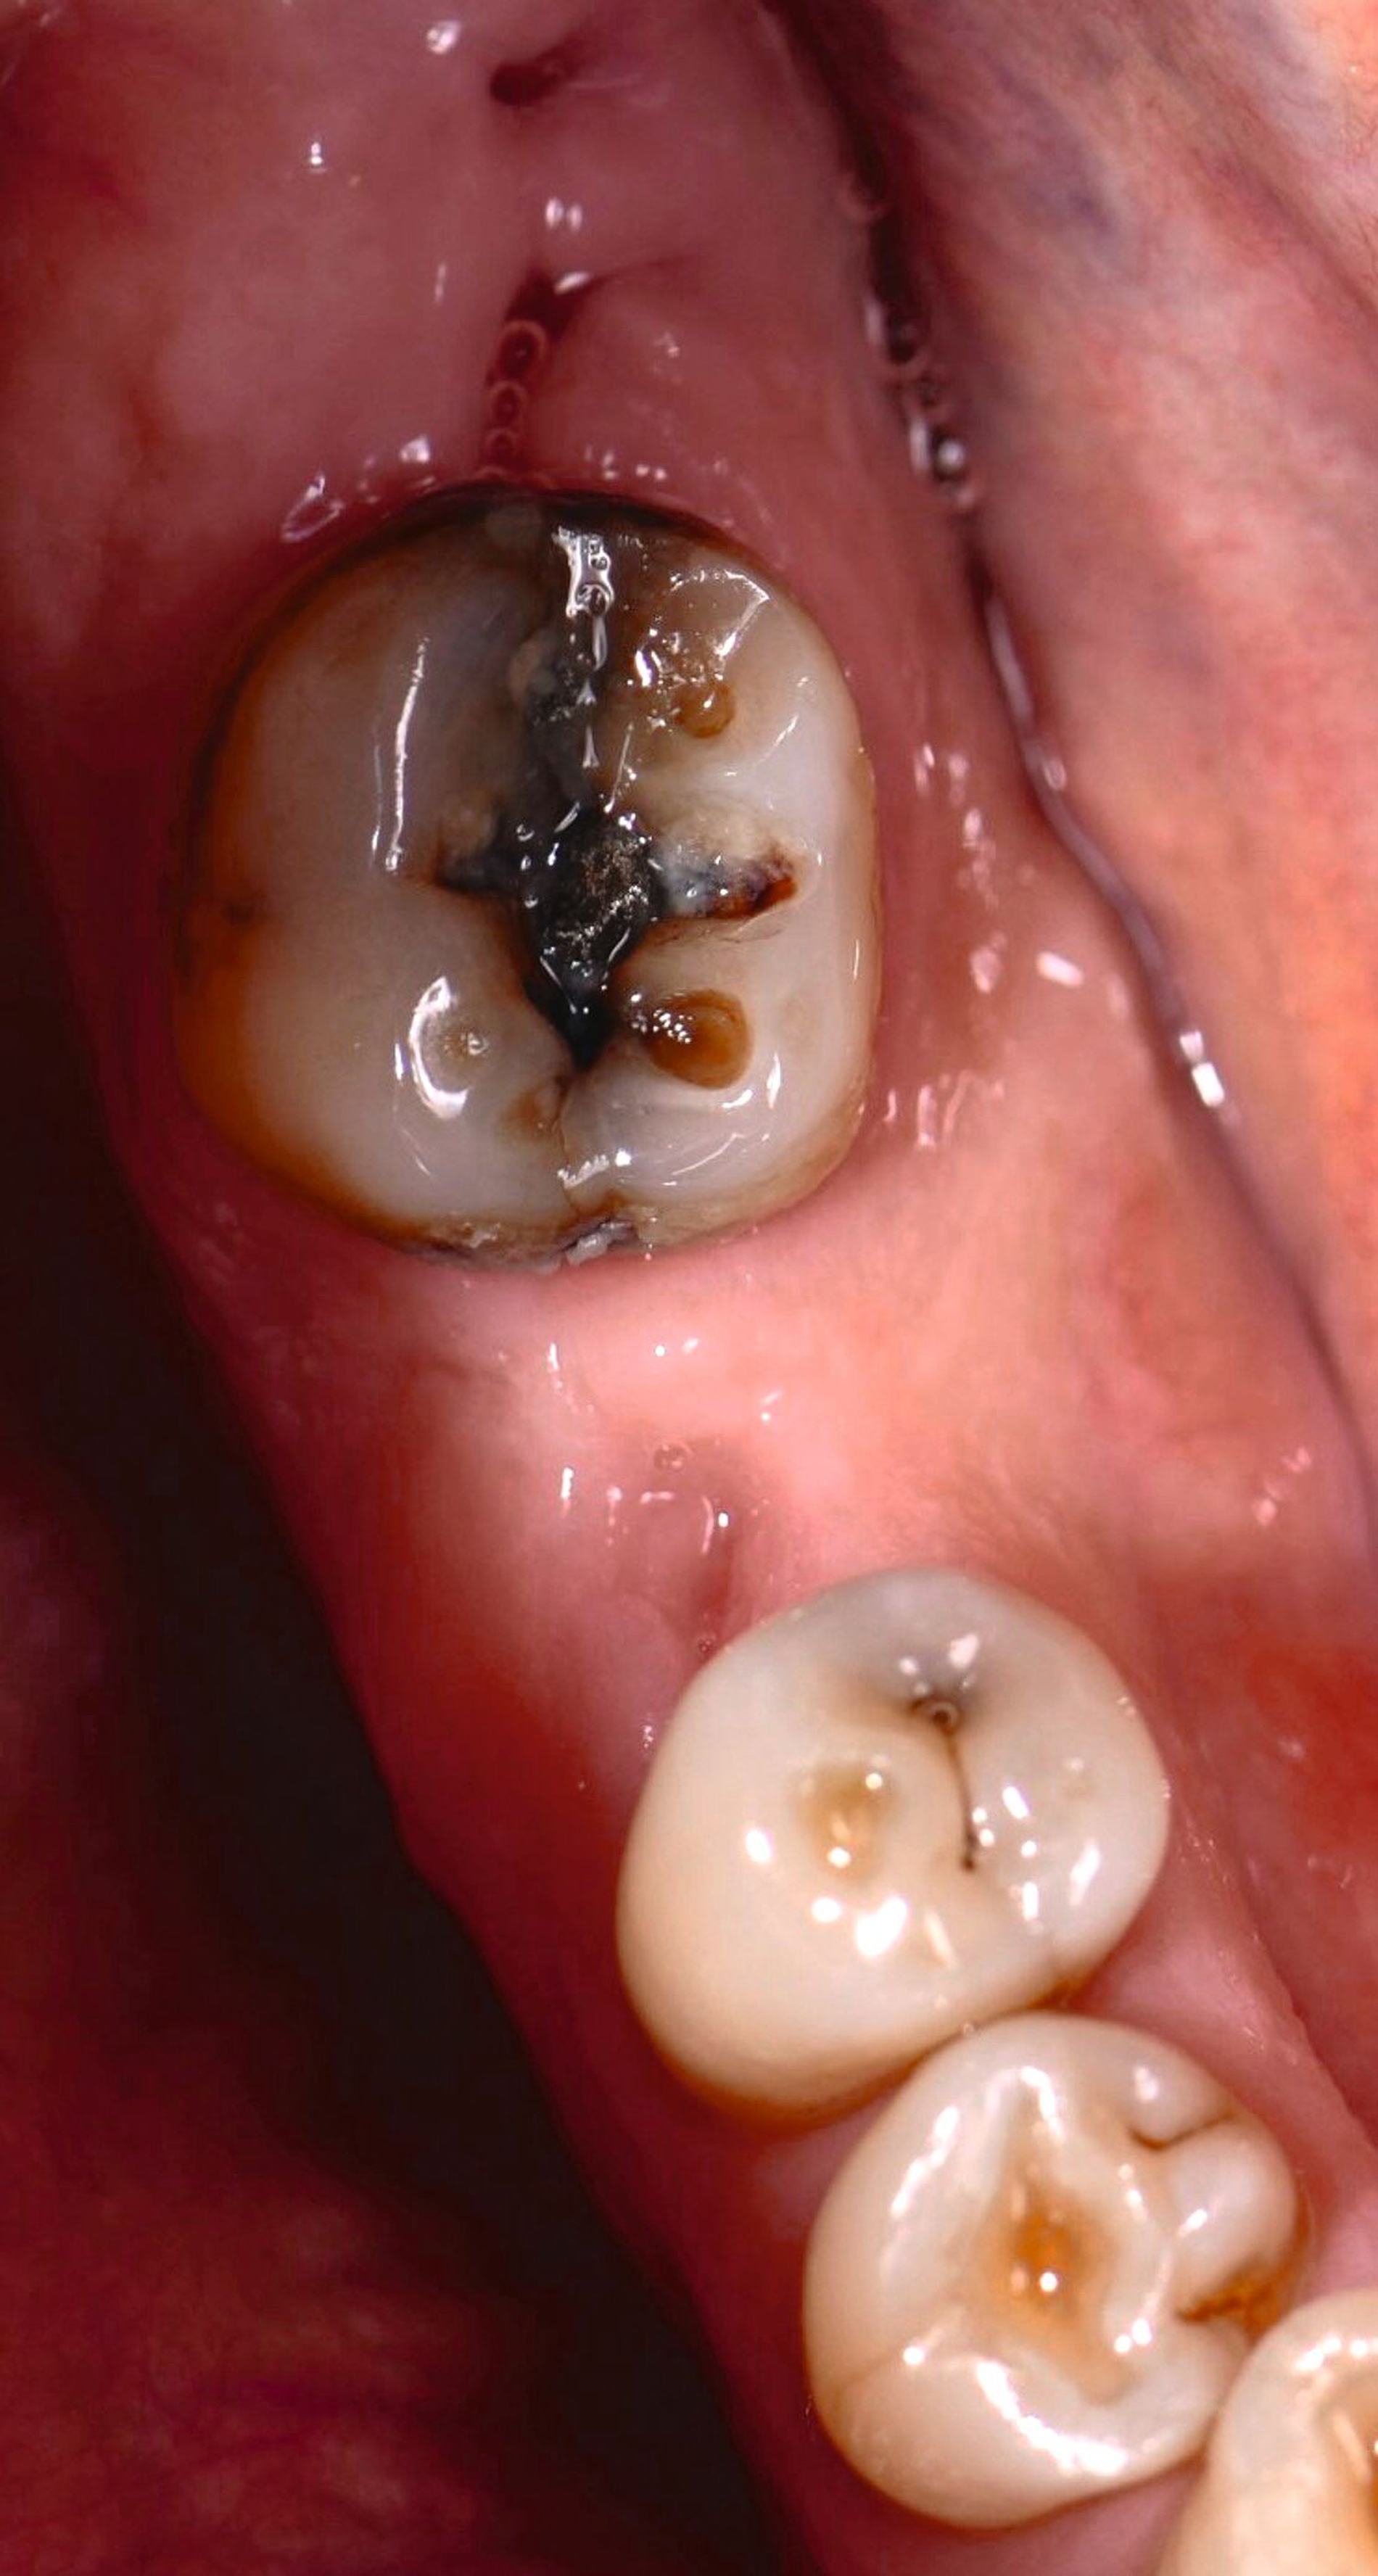

Nach der Beurteilung der chirurgischen Risiken werden die prothetischen Voraussetzungen evaluiert. Ist ausreichend Platz für die Idealgestaltung der zukünftigen Restauration vorhanden (sowohl was die Anatomie als auch was die funktionelle Gestaltung angeht), stellt dies die S-Variante dar. Im vorliegenden Fall zeigt sich der Zahn 47 kariös sowie teilweise rotiert und mesioincliniert, wodurch der prothetische Raum für 46 partiell verschlossen ist (Abbildung 2). Wir entschieden uns daher für eine simultane Versorgung von Zahn 47 mit einer Teilkrone. Ziel war es, die Insertionsachse der Implantatkrone und die Reinigbarkeit der Interdentalräume zu optimieren (Abbildung 3).